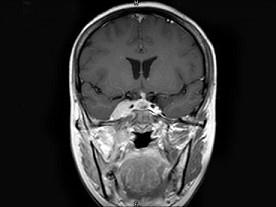

问题 女,34岁。右侧听力下降,耳鸣2个月。MRI平扫及增强扫描如图示,最可能的诊断是 ( )

选项 A、动脉瘤 B、未见异常 C、脑膜瘤 D、神经源性肿瘤 E、鼻咽癌

答案 E